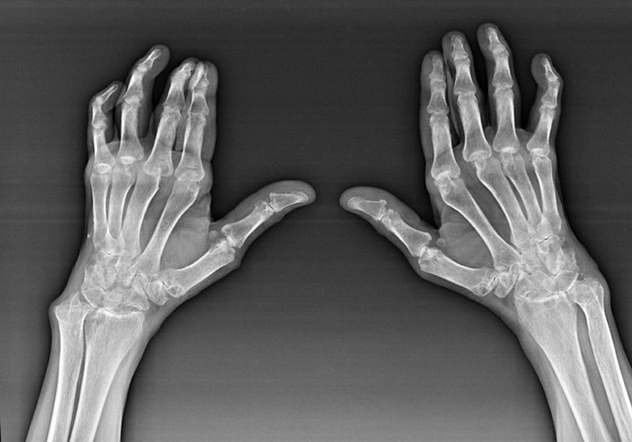

Polyarthrite rhumatoïde

La polyarthrite rhumatoïde est une maladie dans laquelle le système immunitaire humain endommage les propres tissus du corps. En d'autres termes, la polyarthrite rhumatoïde est une pathologie auto-immune. Cette maladie est également systémique, car de nombreux tissus en sont affectés (muscles, articulations, vaisseaux, etc.) et les organes (Cœur, reins, poumons, etc.) dans le corps.

Malgré le fait que la polyarthrite rhumatoïde est une maladie systémique sous elle, dans une plus grande mesure, les articulations souffrent, tandis que la lésion d'autres tissus et organes est en arrière-plan. Avec cette maladie, presque tous les types d'articulations de pinceau peuvent être affectés (marques, paths carpiens, métacarpaux-phalanx, articulations inter-phalanx). La lésion est généralement symétrique (ceux. Les mêmes articulations sont affectées) sur les deux mains, accompagnée de gonflement, de douleur dans les articulations endommagées. Le matin, lors de la levée du lit, il y a une certaine raideur dans les articulations affectées, qui peuvent durer environ 1 heure, puis disparaître sans trace.

Très souvent avec une arthrite rhumatismale près des articulations affectées de la brosse (le plus souvent les articulations piano-phalanx, inter-phalanx)) Les nodules rhumatoïdes apparaissent. Ils sont une formation arrondie située sous la peau. Sur la brosse, ces formations surviennent le plus souvent à l'arrière. Sur la palpation, ils sont denses, inactifs, indolores. Le nombre d'entre eux peut varier.